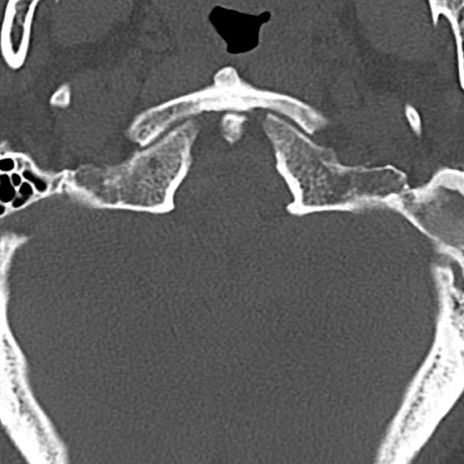

頚椎CT

横断像